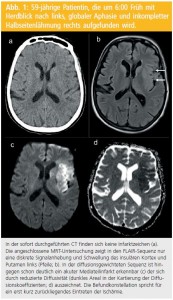

Diffusionsgewichtete Bildgebung (DWI): Ein überragender Vorteil im Vergleich zur CT hat sich jedoch erst mit Einführung des DWI (Diffusion-weighted Imaging) ergeben, das auf der Abbildung der Mobilität der Wasserstoffprotonen im Gewebe beruht. Die Diffusivität der Wasserstoffprotonen nimmt bei akuter Ischämie sehr rasch ab, sodass Gewebeveränderungen mittels DWI bereits nach 20 Minuten als Areale hoher Signalintensität und damit früher eindeutig zu detektieren sind als dies mit konventioneller MRT oder CT möglich ist (Abb. 1).

Eine Hyperintensität in der DWI ist nur in Ausnahmefällen reversibel und mündet somit meist in einen Infarkt. Zudem ist die Reduktion der Diffusivität, die anhand der Kartierung der Diffusionskoeffizienten überprüft werden kann, fast exklusiv bei akuten ischämischen Veränderungen zu finden und damit ein recht spezifischer Befund, der insbesondere auch hilft, akute von alten Infarkten abzugrenzen (Abb. 2). Dies hat die DWI zu einer Routinesequenz in der Abklärung des akuten Schlaganfalls gemacht.